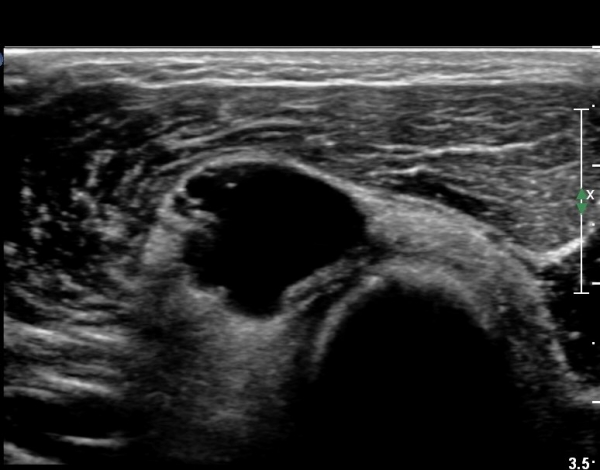

ÃÊÀ½ÆÄ °Ë»ç

¿ä°ñµÎ ±ÙÀ§ºÎ Ⱦ´Ü¸é°Ë»ç»ó Èİñ°£ ½Å°æ ³»ÃøÀ¸·Î ÀÛÀº ³¶Á¾ÀÌ °üÂûµÈ´Ù(»çÁø 1).